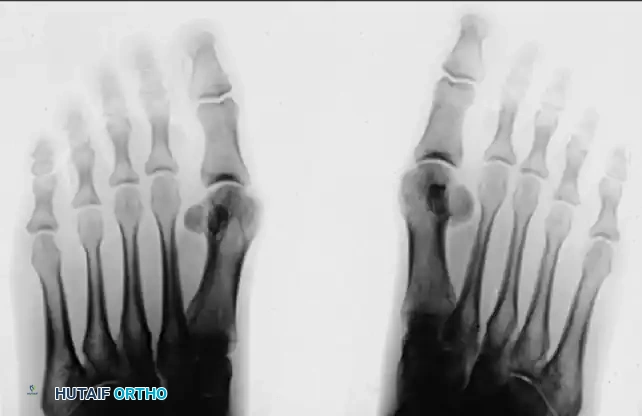

Anteroposterior (AP) and Oblique Views

Standing AP views allow for a comparison of the sesamoids. This is especially helpful if a fracture is suspected but a bipartite sesamoid is present. Accessory sesamoids are normal, although uncommon, findings.

FIGURE 81-100 A: Standing anteroposterior view of both feet on the same cassette allows comparison of sesamoids. This is especially helpful if a fracture is suspected but a bipartite sesamoid is present. Accessory sesamoids (arrows) are normal, although uncommon, findings.